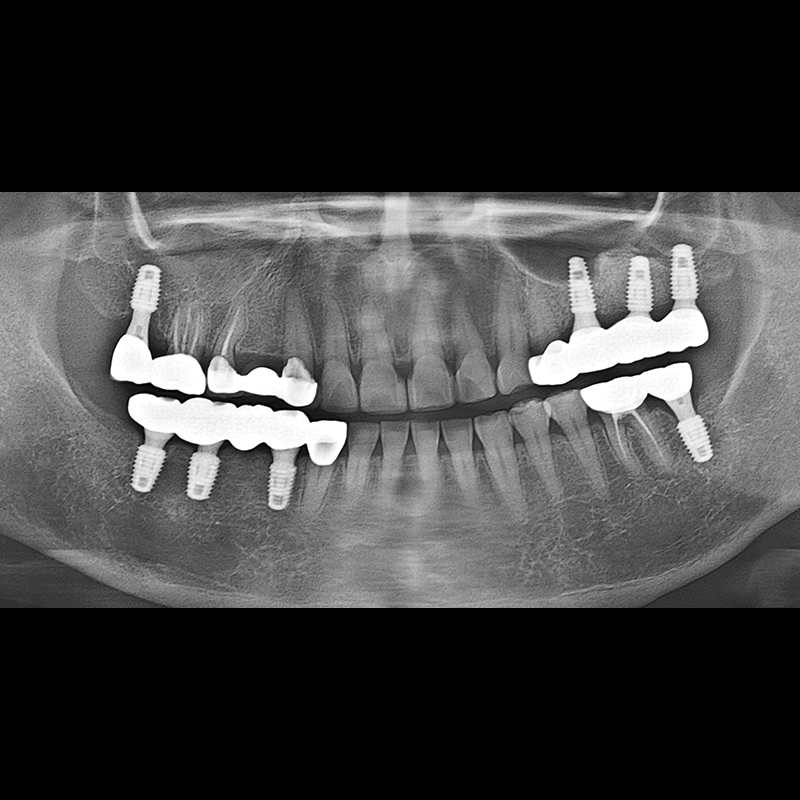

IMPLANT

BEFORE AFTER

Implant before and after 2025.05.30

Implants were placed in the missing tooth and in the tooth position where it was difficult to save.